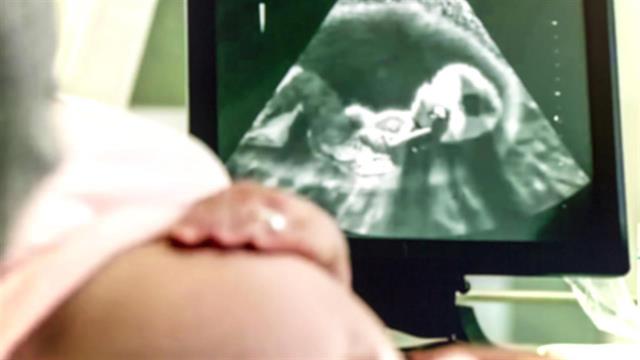

Ένας από τους ίσως μεγαλύτερους φόβους μιας εγκύου είναι ο φόβος του πόνου κατά τον τοκετό, φόβος που πολλές φορές επιδεινώνεται από την καλοπροαίρετη ευχή « Μ’ έναν πόνο», που συγγενείς και φίλοι εύχονται στη μέλλουσα μητέρα. Πόσο όμως οι ωδίνες υπάρχουν και σε ποιο βαθμό;

Ο Μαιευτήρας, Δρ. Νικόλαος Σκαρτάδος, Μαιευτήρας, Χειρουργός-Γυναικολόγος, Διδάκτωρ της Ιατρικής Σχολής του Πανεπιστημίου Αθηνών, θεωρεί  καταρχάς πως ο φόβος για τον πόνο που συνοδεύει τον τοκετό ενδεχόμενα να επηρεάσει ψυχολογικά την χαρούμενη προσμονή για την έλευση του νέου μέλους στην οικογένεια της εγκύου.

«Η έννοια του πόνου έχει διαφορετική διάσταση για κάθε γυναίκα, με κάποιες να μη θυμούνται καν αν πόνεσαν και άλλες να περιγράφουν τον τοκετό με τα..μελανότερα χρώματα», διευκρινίζει ο γιατρός και συμπληρώνει: «Η αλήθεια είναι πως υπάρχουν επώδυνες συσπάσεις της μήτρας που μεταφέρονται με τα νεύρα στον νωτιαίο μυελό και από εκεί στον εγκέφαλο, όπου και γίνονται αντιληπτοί από την έγκυο».

Παράλληλα, οι πόνοι αυτοί οφείλονται στην ίδια τη διαδρομή του εμβρύου στον ερχομό του στον κόσμου, δεδομένου ότι πιέζει ιστούς και νεύρα. «Ο πόνος αυτός» τονίζει ο κ. Σκαρτάδος, «δεν ‘’φοβίζει» τόσο για την έντασή του, όσο για τη συχνότητά του, η οποία όντας επαναλαμβανόμενη δημιουργεί μια ταλαιπωρία στη γυναίκα».